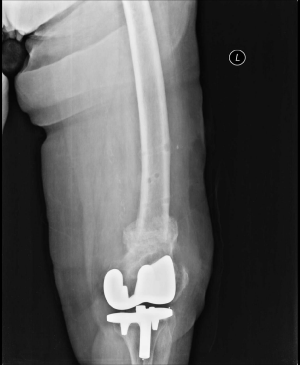

Radiographs demonstrated a fracture at the supracondylar region of the femur with significant displacement and well-functioning prosthesis (Figures 1 and 2). According to Rorabeck classification this fracture was classified as type two.8 Internal fixation was planned, however, due to multiple co-morbidities and relatively high risk of anaesthesia, a decision was made to manage the fracture by external fixation.

Figure 1: The preoperative AP (1) and lateral (2) x-rays of the patient demonstrating a Rorabeck type 2 supracondylar displaced periprosthetic fracture